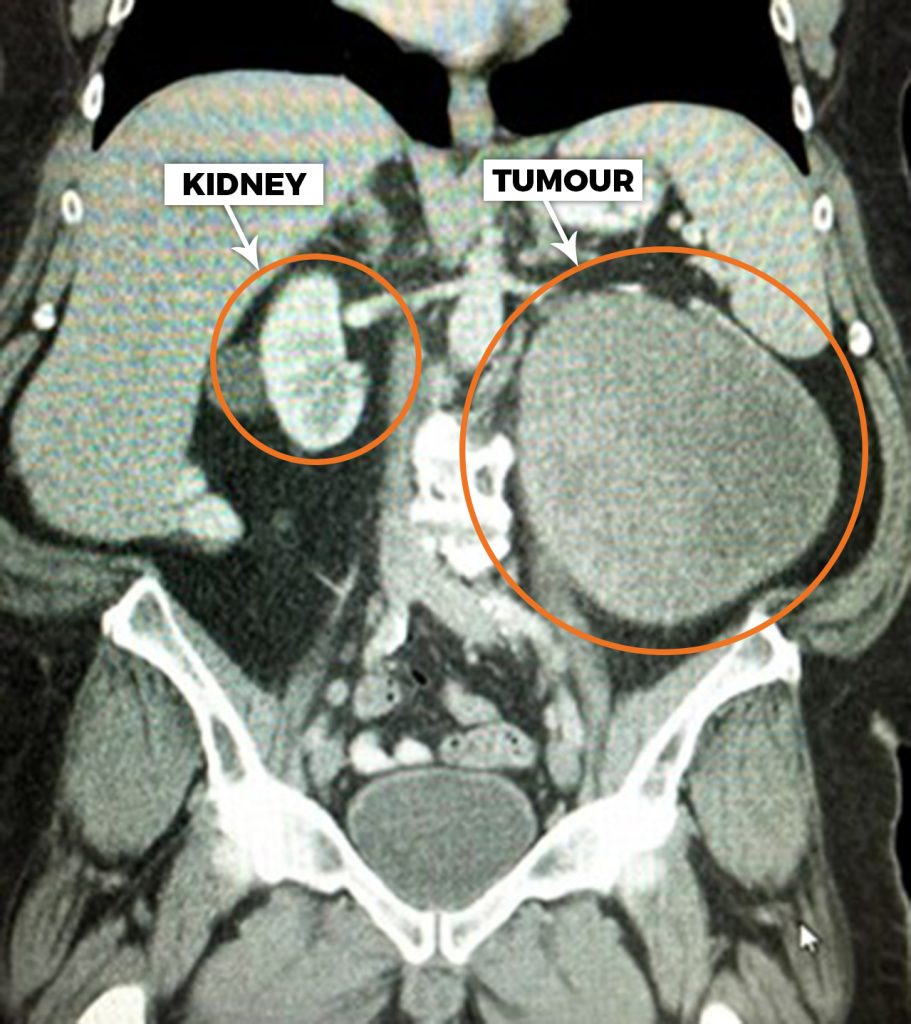

Her work has also included managing exceptional cases, such as the laparoscopic removal of one of the largest documented kidney tumours of its kind, demonstrating that even extreme cases can sometimes still be approached using minimally invasive techniques when carefully planned and performed by an experienced surgeon.

Laparoscopic removal of one of the largest documented kidney tumours of its kind.